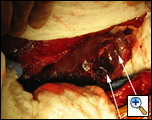

In the operating room, a right thoracotomy through the 5th intercostal space, 5th rib resection, and an intercostal muscle flap harvest was performed. Upon entering the chest, a large abscess was present surrounding the distal esophagus, with an empyema and widespread posterior mediastinitis. The esophagus exhibited full-thickness necrosis extending from the gastroesophageal junction to 5 cm below the thoracic inlet and was filled with clotted blood. There was a perforation of the distal esophagus extending from 10cm below the carina to the gastroesophageal junction (Figures 3A&B). The esophagus was resected with proximal and distal transections completed with an endoGIA 45 (3.5mm) stapling device. The posterior mediastinum was debrided and the right lung decorticated. Three chest tubes were placed, and a naso-gastric tube was placed within the cervical esophagus and both jejunostomy and gastrostomy tubes were placed. Forty eight hours later and off pressors, the patient was taken to the operating room for creation of a left cervical esophagostomy.